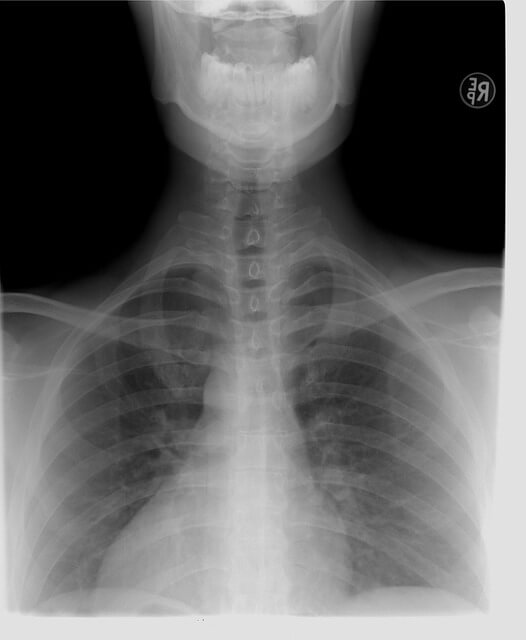

폐결핵

검사방법 : 흉부 엑스레이 촬영

결핵은 세균에 의해 발생하는 감염병으로

주로 폐에서 발병하나 신장이나 신경, 뼈 등에서도 발생할 수 있어 흉부 엑스레이를 촬영하여 검사합니다.